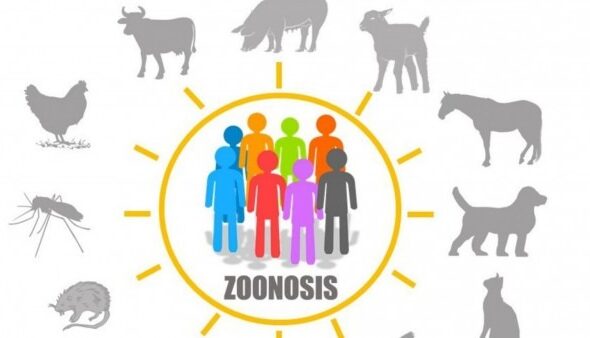

Argentina pierde alrededor de $60.000 millones en el sector ganadero debido a problemas sanitarios.